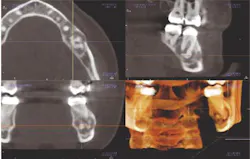

The second major change comes in interpreting the images. You have to take the time to understand the anatomy, even if you are using a machine that allows for focused volume views, such as the CS 9300 (Carestream Dental), which you're familiar with. Take the time to learn the science, the 3-D radiographic anatomy and radiographic interpretation, radiation dosimetry, and 3-D imaging.

Above: Images from the Carestream Dental CS 9300